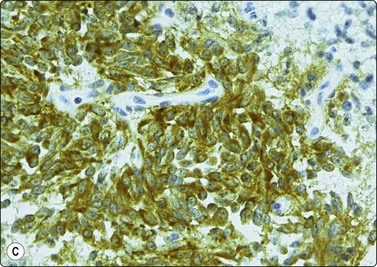

Immunocytochemistry37,40-43

The increasing commercial availability of monoclonal antisera to a variety of proteins and other cell products, which are more or less specific to different cell lines, is probably the most important recent development in diagnostic cytology. The demonstration and identification of such cell products in smears and cell blocks is of immense value as it offers a means of objectively recognizing the line of differentiation shown by the cells. Immunostaining may allow a confident specific diagnosis even on relatively scanty material (e.g. medullary carcinoma of thyroid, Fig. 2.23). Immune markers are extremely useful in the differentiation between anaplastic carcinoma, neuroendocrine tumors, malignant lymphoma and amelanotic melanoma (cytokeratin, EMA, chromogranin, NSE, LCA, S-100, etc.), in the search for a primary in metastatic malignancies (e.g. differential staining for a number of cytokeratins), and in the histogenetic typing of mesenchymal tumors (see Chapter 15). Markers for B and T cells, immunoglobulins and light chains are indispensable in the typing of lymphoma (see Chapter 5). Monoclonal antibodies to certain tumor antigens have been found to be useful in the distinction between malignant and benign epithelial cells.44 A list of the most common immune markers used in FNAC is presented in Table 2.4. Immunoprofiles are also included with other diagnostic criteria for most entities in the following chapters.

image

Fig. 2.23 Immunoperoxidase staining

Strongly positive cytoplasmic staining for calcitonin in a direct FNB smear from medullary carcinoma of thyroid (HP).

Sections of cell blocks fixed in 10% formalin and transferred to TBS for immunoperoxidase staining, or tissue fragments obtained by core needle biopsy, in general provide the best material for immunocytochemistry. Cell blocks and core biopsies offer the great advantage of a large number of sections, sufficient for a panel of markers and for the indispensable negative controls. On the other hand, some antigens are not well preserved in formalin-fixed material, but are demonstrable in air-dried smears. In stroma-rich tumors, FNB selectively samples the abnormal cells detached from the stroma, which sometimes facilitates interpretation.

If tissue fragments are not available, immunostaining can be performed on direct smears, or on smears derived from a cell suspension using the cytocentrifuge (Fig. 2.24). Alcohol-fixed smears are usually preferable to air-dried smears. ThinPrep slides of FNAC material have been found highly suitable for immunocytochemical staining.45,46 This technique has the advantage of eliminating background interference by blood and debris (see liquid-based cytology below). The limited number of tests possible when only smears are available can be increased by circling areas 3 mm apart on the same slide with a diamond pencil and wiping the smear between. This allows 2–3 different tests per slide. De-stained previously Pap-stained smears can be used, although poor attachment of the cells to the slide can be a problem.47 Sections of alcohol-fixed and paraffin-embedded cell ‘buttons’ are a good alternative to tissue cores and cell blocks (Fig. 2.25 and see Fig. 2.16).

image image

Fig. 2.24 Immunoperoxidase staining

Smears of non-Hodgkin’s lymphoma. (A) Direct smear; interpretation difficult due to background staining caused by fragmentation of cytoplasm; (B) Cytocentrifuge preparation; positive staining distinctly related to individual cells (HP).

Fig. 2.25 Immunoperoxidase staining

‘Cell button’ of FNB sample of non-Hodgkin’s B-cell lymphoma; (A) Tissue section, H&E; (B) Positive staining with a pan-B marker; (C) negative staining with a pan-T marker (IP).

The avidin–biotin complex method is the most commonly used with both monoclonal and polyclonal primary antibodies. Diaminobenzidine is used as the marker dye. Immunoalkaline phosphatase staining appears to offer several advantages in cytological preparations. Commercially produced kits have made immunohistochemistry a relatively simple method available to any cytology laboratory, and an ever-increasing number of antisera are being marketed in this form. Appropriate controls are crucial to achieving diagnostic accuracy.48 A review of immunostaining techniques adapted to cytological preparations can be found in Diagnostic Cytopathology.44

Interpretation of immunohistochemical staining is often more difficult in smears than in histological sections because the cytoplasm of neoplastic cells detached from the stroma is often fragile and dispersed in the background. Blood, serum or secretory products are often superimposed on the cells. All this makes it difficult to ascribe any positive staining to specific, identifiable cells. Ways to overcome the difficulties are discussed in the paper by Suthipintawong and Leong referred to above.44 When examining the smears, it is best to focus on tissue fragments, in which the cells are protected leaving cell membranes and cytoplasm intact. Background staining is a lesser problem in cytospin preparations if the cells are washed, in ThinPrep smears, and in paraffin sections from a cell ‘button’. The results of immunocytochemistry must be interpreted with caution and in the context of conventional cytomorphology and clinical data.49